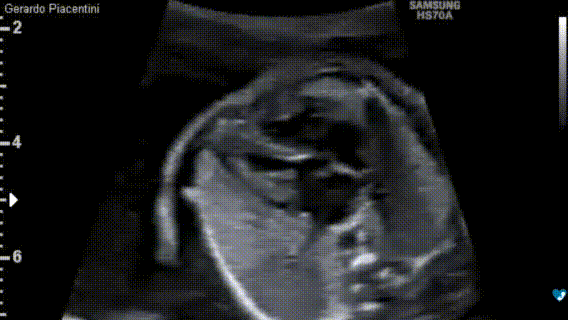

Ecocardiografia fetale - 17 settimane